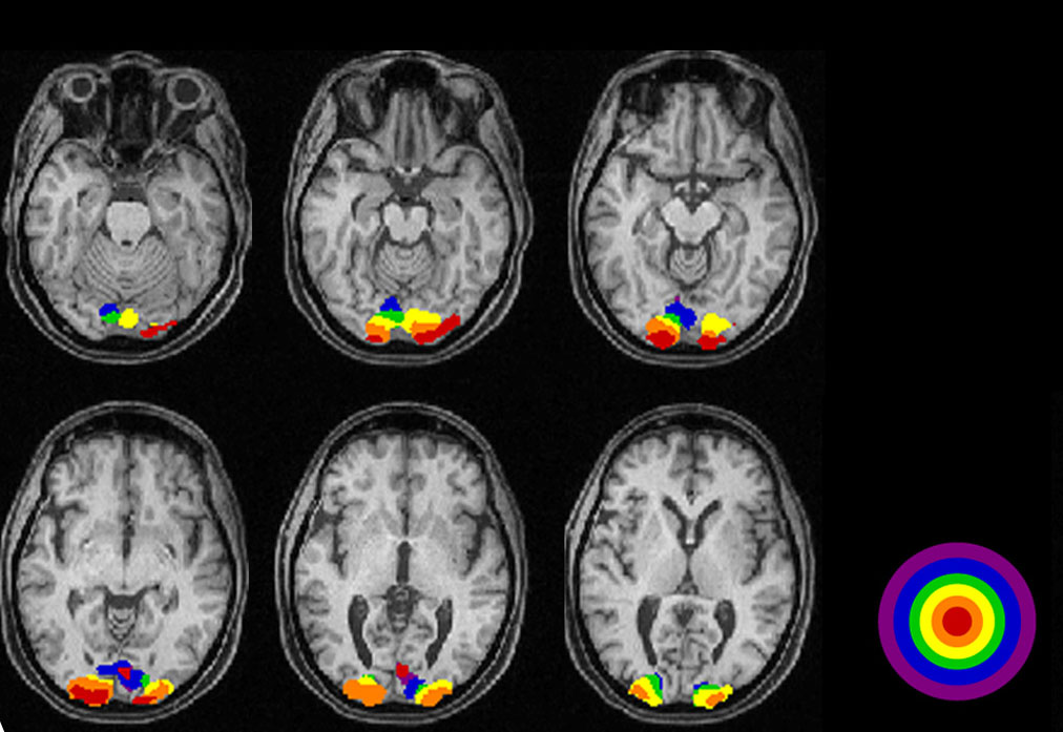

Functional MRI

active neurons have increased blood flow

detect changes in regional blood flow and blood O2 in the brain